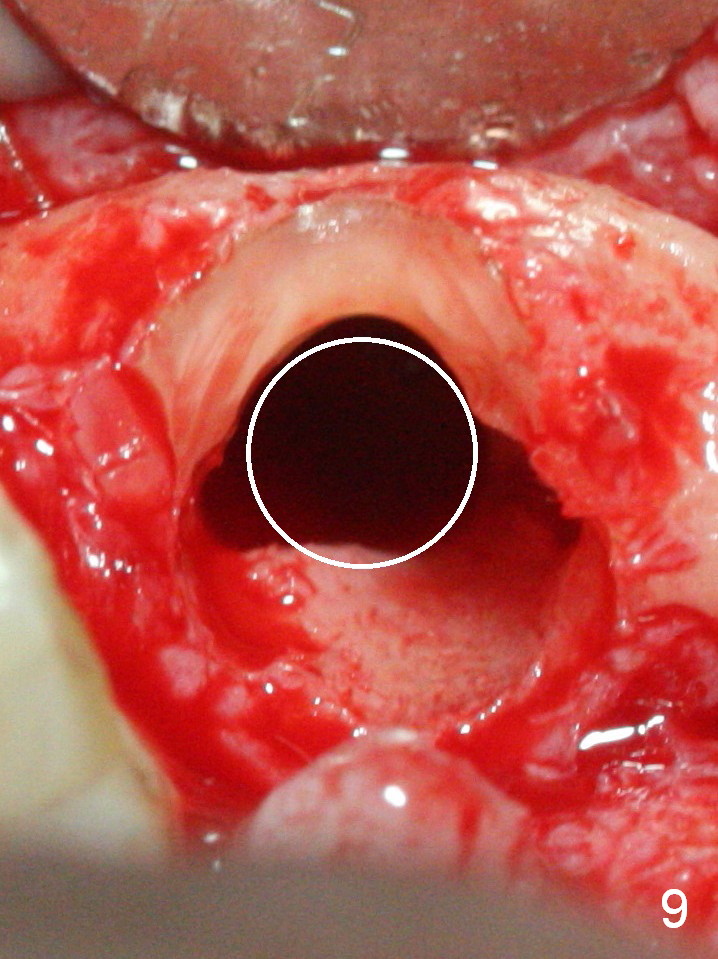

When the bridge is sectioned between #7 and 8, the tooth #6 is found non-salvageable (Fig.1). Incision shows the atrophic buccal plate at #7 (Fig.2 arrowheads); to prevent the same feature from happening at #6 with thin buccal plate, the most buccal portion of the root is preserved (socket shield (Fig.2-4: *)). The initial osteotomy is established in the palatal slope at #6 (Fig.5 circle) with 1.5 mm drill (Fig.6,7). A portion of the root is visible in Fig.6 (arrowheads). After sequential osteotomy with 2 mm, 3 mm (Fig.8) and 3.2 mm drills, a 4x15 mm implant is placed (Fig.10). To accommodate the cross bite, the coronal portion of the implant (Fig.9 white circle) is positioned close to the socket shield. It appears that the shield prevents the implant from encroaching the buccal plate.